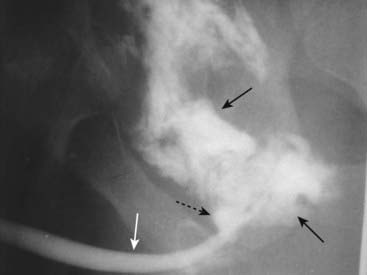

image

Figure 17-13 Urethral trauma.

Contrast instilled retrograde through the penile urethra (solid white arrow) is seen to leak from the posterior urethra secondary to a perforation (dotted black arrow) and collects outside of the urinary system in the perineum and extraperitoneal bladder spaces (solid black arrows).